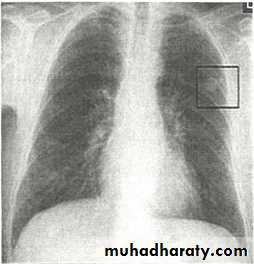

•Nodular (coin) lesion in the left upper lung with irregular edge (most probably cancinoma